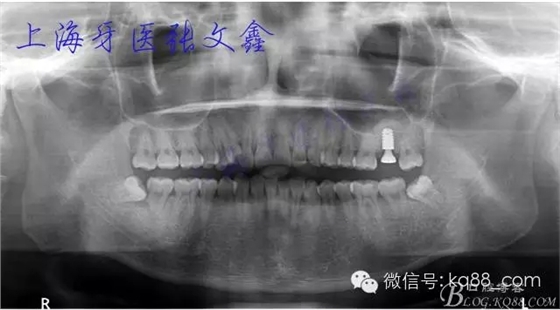

術后全景片